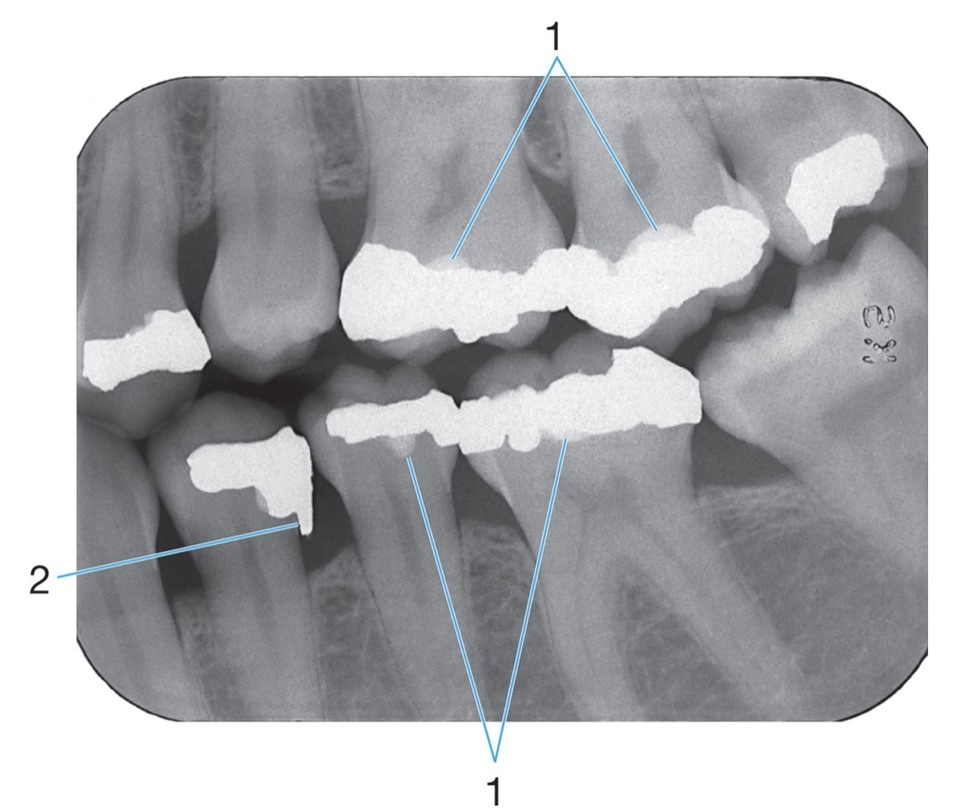

2.

Radiopaque amalgam restorations

Mylohyoid ridge

1.

Full metal crowns form bridge abutments